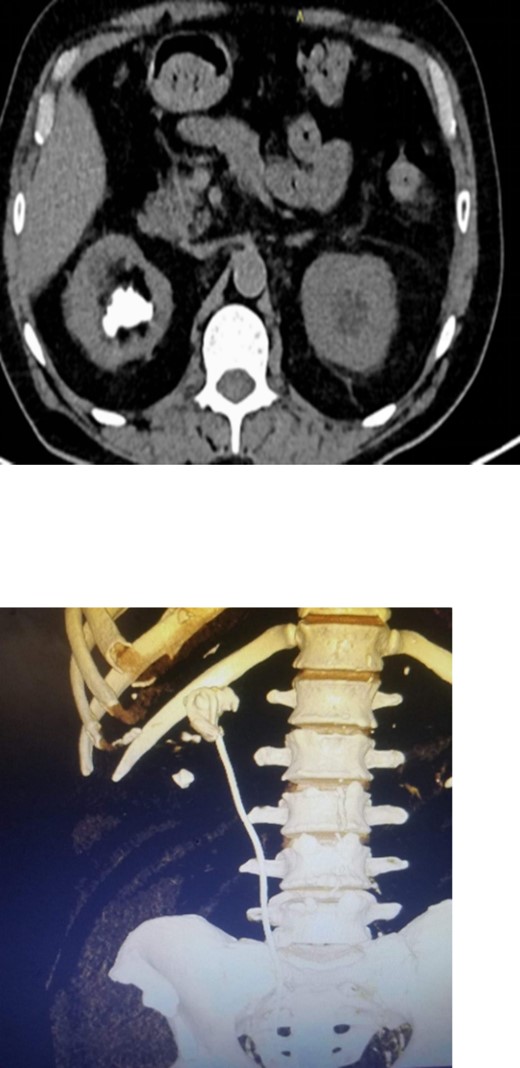

On physical examination, he had normal vital signs, no fever, and exhibited mild tenderness in the suprapubic area and right costovertebral angle. The results of the laboratory tests were normal, and the serum creatinine level was 0.8 mg/dl. Urine culture was negative for bacteria. Preoperative abdominal and pelvic ultrasound revealed two right renal stones, one measuring 4 cm in the upper pole and 2 cm in the lower pole with mild hydronephrosis, along with a large bladder stone measuring 6 cm, and a shadow of a double J stent. A computed tomography (CT) scan confirmed the presence of a 4 cm upper pole renal stone, a 1.8 cm lower pole renal stone, significant proximal pigtail calcification with mild hydronephrosis (Fig. 1A and B), and a 6 cm bladder stone deeply embedded in the distal pigtail (Fig. 2A and B). Additionally, small intrarenal stones were observed on the left side, along with a proximal ureteric stone measuring 8 mm by 9 mm with mild hydronephrosis.

Non-contrast CT scan showed intra-renal stone with significant proximal pigtail calcification and mild degree of hydronephrosis.